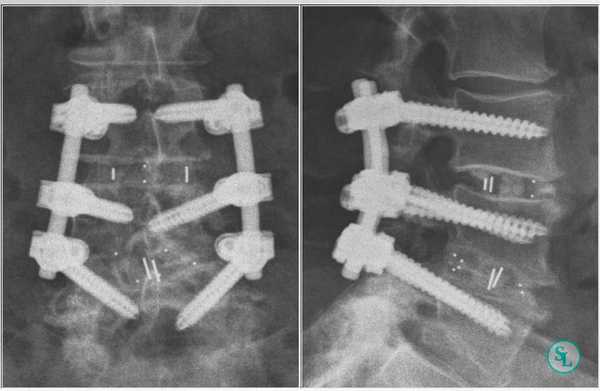

Но особенно результативным, по данным проведенных исследований, является межтеловой спондилодез. Поскольку тела позвонков значительно лучше снабжаются кровью, имеют большее количество клеточных элементов и отличаются высоким потенциалом к образованию новой костной ткани, имплантированные между ними объекты приживаются значительно лучше, чем установленные между отростками позвонков. При таком способе фиксации успешного спондилодеза удается добиться в 96% случаев. В противном случае позвонки могут не срастись, что приведет к сохранению болей в спине, а в дальнейшем к тяжелым последствиям.

В подавляющем большинстве случаев операции на поясничном отделе позвоночника выполняются задним доступом с выбором межтелового способа фиксации позвонков. Вмешательство через передний доступ осуществляют исключительно в сложных клинических случаях и при оскольчатых переломах.

Чтобы иммобилизация позвоночно-двигательного сегмента была максимально надежной, нередко операция дополняется выполнением транспедикулярной фиксации. В таком случае устанавливаются специальные металлические конструкции, которые еще более упрочняют скрепление тел позвонков.